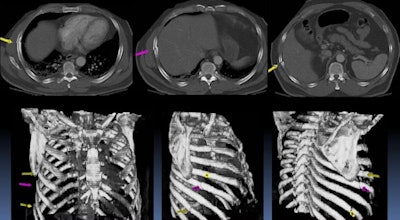

| Axial CT images show three fractures involving the sixth, seventh, and ninth ribs (arrows), while the bony thorax and rib fractures are also displayed in 3D volume-rendered images. The use of CAD to automatically label and index fractured ribs could save time during the interpretation and reporting process. All images courtesy of Dr. Ty Bae, Ph.D. |

A number of published studies have found CAD to be promising in counting ribs and vertebrae on CT. All have used only normal bony structures, however, Bae said.